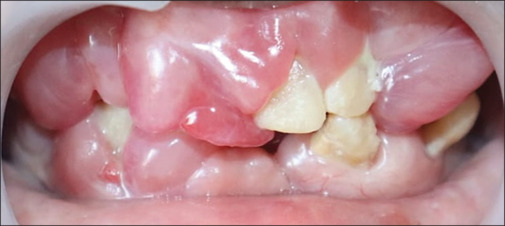

药物性牙龈肿大通常是由于患者对处方药的副作用缺乏认识而发生的。本病例报告详细介绍了一位50岁女性的罕见的大量药物引起的牙龈过度生长,通过多学科方法,包括手术干预和假肢康复,成功地进行了治疗。手术治疗包括多次摘除和切除多余组织。手术后两足弓完全愈合,患者接受了假肢康复治疗,无复发迹象。此类病例的有效管理依赖于患者咨询和适当的药物替代。提高对某些药物的副作用以及全身和口腔健康之间的联系的认识对于预防这类牙龈肿大的病例至关重要。

Drug-induced gingival enlargement often occurs due to patient's lack of awareness about the side effects of prescribed medications. This case report details an unusual instance of massive drug-induced gingival overgrowth in a 50-year-old female, successfully managed through a multidisciplinary approach, including surgical intervention and prosthetic rehabilitation. The surgical treatment involved multiple extractions and the excision of excessive tissue. Both arches healed completely after surgery, and the patient underwent prosthetic rehabilitation, with no signs of recurrence. Effective management of such cases relies on patient counseling and appropriate drug substitution. Increasing awareness about the side effects of certain medications and the connection between systemic and oral health is crucial to prevent such cases of gingival enlargement.